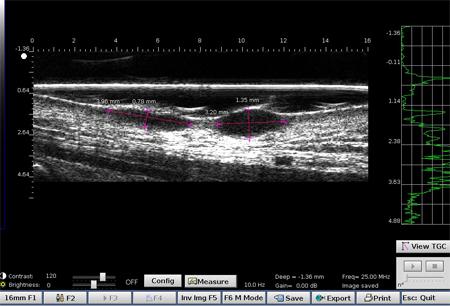

Melanomas Ecografía

Hipoecoica , con ecos de baja densidad. El eco de entrada no está muy marcado o ausente (ausencia de queratosis, ulceración) Melanoma ulcerado en el antebrazo (grosor medido a 3,68 mm en ecografía, grosor histológico). Lesión que infiltra la dermis. Melanoma en la oreja Carcinoma de células basalesCarcinoma de células basales en la frente (por encima de la arteria temporal)Carcinoma de células basales en la cara por encima del mastoidesCarcinomasuperficialCarcinoma pigmentado Nevo dérmico Lesión hipoecoica con muchos ecos, borde con la dermis adyacente mal definidoHistiocitofibroma  Lesión hipoecoica , pobremente limitada con muchos ecos.